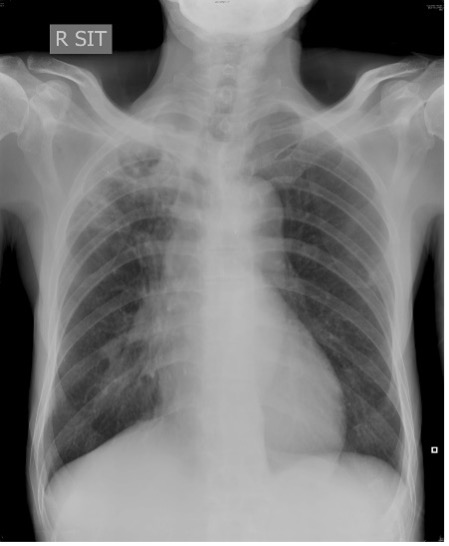

- X光肺片或電腦掃描檢查

- 常見肺部放射線學的變化

- 結節支氣管擴張